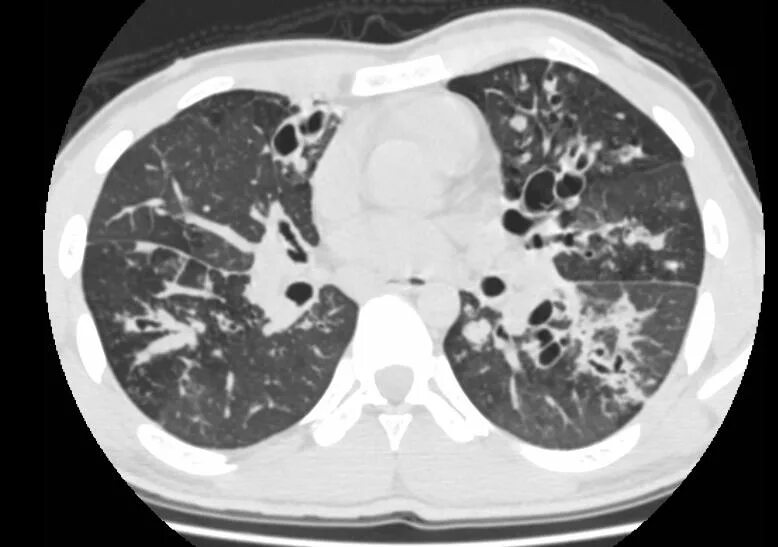

Фиброз кт